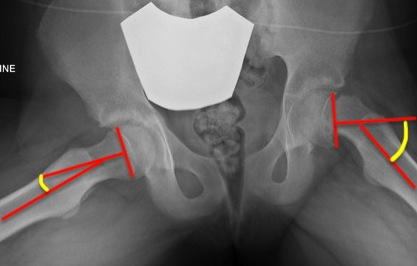

Southwick classification

Southwick Angle / Slip Angle

- epiphyseal-diaphyseal angle on frog leg lateral

- mild <30°

- moderate 30- 50°

- severe >50°

Mild Moderate Severe